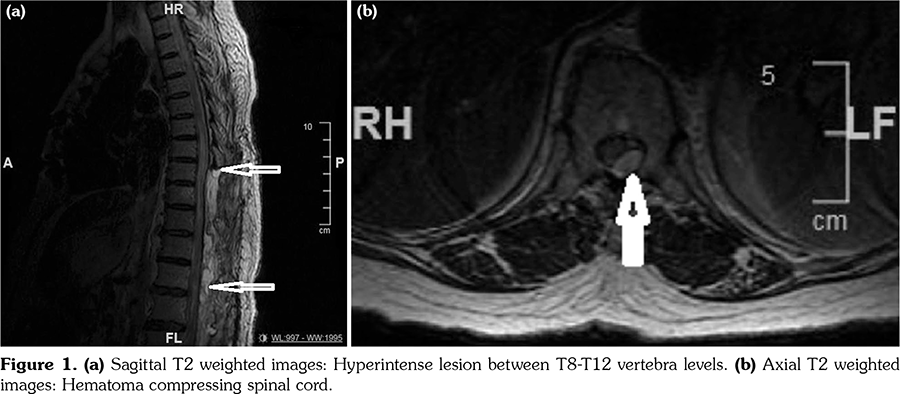

A 56-year-old female patient with RA for the last 18 years had received methotrexate, methylprednisolone, leflunomide, etanercept, infliximab, and adalimumab in the past but all the drugs were discontinued due to inadequate response. TCZ therapy was started with an 8 mg/kg/month infusion. She had also been using warfarin sodium due to grade 2 aortic insufficiency and mitral valve prosthesis for five years. The patient did not use any other drugs. After the 20th day of the fourth trial of TCZ infusion, the patient was admitted to the emergency department with sudden back pain, weakness, and numbness in her legs, bladder and bowel dysfunction. There was no history of trauma. Her blood pressure was 130/90 mmHg. Neurological examination showed the presence of complete paraplegia. Laboratory findings were as follows: hemoglobin: 12.2 g/dL (normal), platelet: 193•109/L (normal), white blood count: 6•109/L (normal), aspartate aminotransferase: 55 U/L (high), alanine aminotransferase: 50 U/L (high), blood urea nitrogen: 16 mg/dL (normal), creatinine: 1.1 mg/dL (normal), INR: 2.1 (normal), C-reactive protein (CRP): 1.2 mg/L (normal). Peripheral blood smear was normal. Factor 13 and fibrinogen levels were normal too. Urgent magnetic resonance imaging (MRI) of the thoracolumbar spine demonstrated an elongated space-occupying mass with convexity to the spinal canal at the level of T8-T12 vertebra which was seen as a hyperintense mass on the T2 weighted images and hypointense on the T1 weighted images (Figure 1). It was observed via immediate exploratory surgery that there was blood in the epidural space and decompressive laminectomy was performed. A written informed consent was obtained from the relatives of patient.